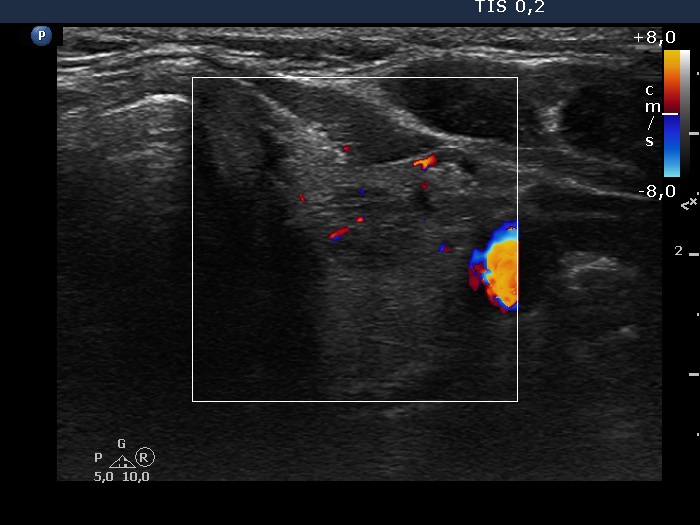

Intranodular hyperechogenic figures - case 1332 (ultrasonographic picture 8)

Lower part of the left lobe, transverse scan, color Doppler mode. The vascularization is not specific.